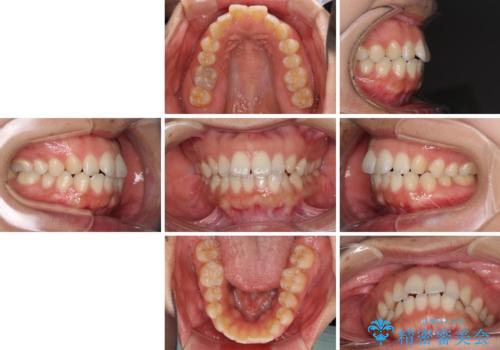

全く目立たないワイヤー矯正 上下リンガル矯正

- 上下の前歯のでこぼこを気にして来院された患者様です。

結婚式が近いこともあり、全く目立たない裏側矯正により口元を整えることとしました。

下顎が左側にずれているため、裏側矯正ということもあり咬み合わせを整えるのに時間がかかってしまいました。